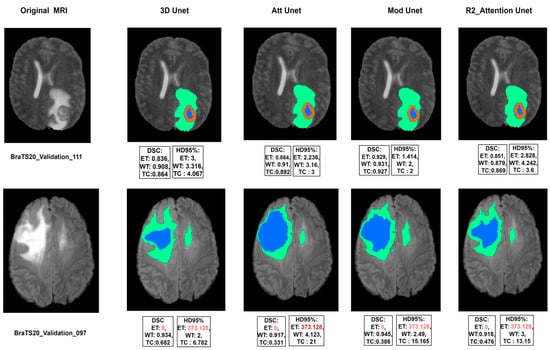

Experimental Training Layout

- 3D U-Net: This architecture consists of four levels of convolutions in both the encoder and decoder. It was proposed in [96].

- Modified 3D U-Net: follows the same attributes as the previous model, but an extra level is added, so the encoder–decoder network uses five levels of convolutions.

- R2 Attention U-Net: Recurrent Residual Attention U-Net was proposed in [97], which adds the recurrent and residual blocks to the first 3D model.

| Model | DSC | HD95% | Parameters | Time | ||||

|---|---|---|---|---|---|---|---|---|

| ET | WT | TC | ET | WT | TC | |||

| 3D U-Net [96] | 0.779 | 0.881 | 0.827 | 27.23 | 7.788 | 8.278 | 23 M | 6 h (1.2 s/sample) |

| Modified U-Net | 0.781 | 0.905 | 0.807 | 26.607 | 5.785 | 18.545 | 26 M | 10 h (3.8 s/sample) |

| Attention U-Net [44] | 0.778 | 0.878 | 0.827 | 26.662 | 7.794 | 8.305 | 23.2 M | 6.2 h (1.7 s/sample) |

| R2 Attention U-Net [97] | 0.7426 | 0.8784 | 0.7993 | 36.653 | 9.228 | 9.95 | 22 M | 5.8 h (0.8 s/sample) |